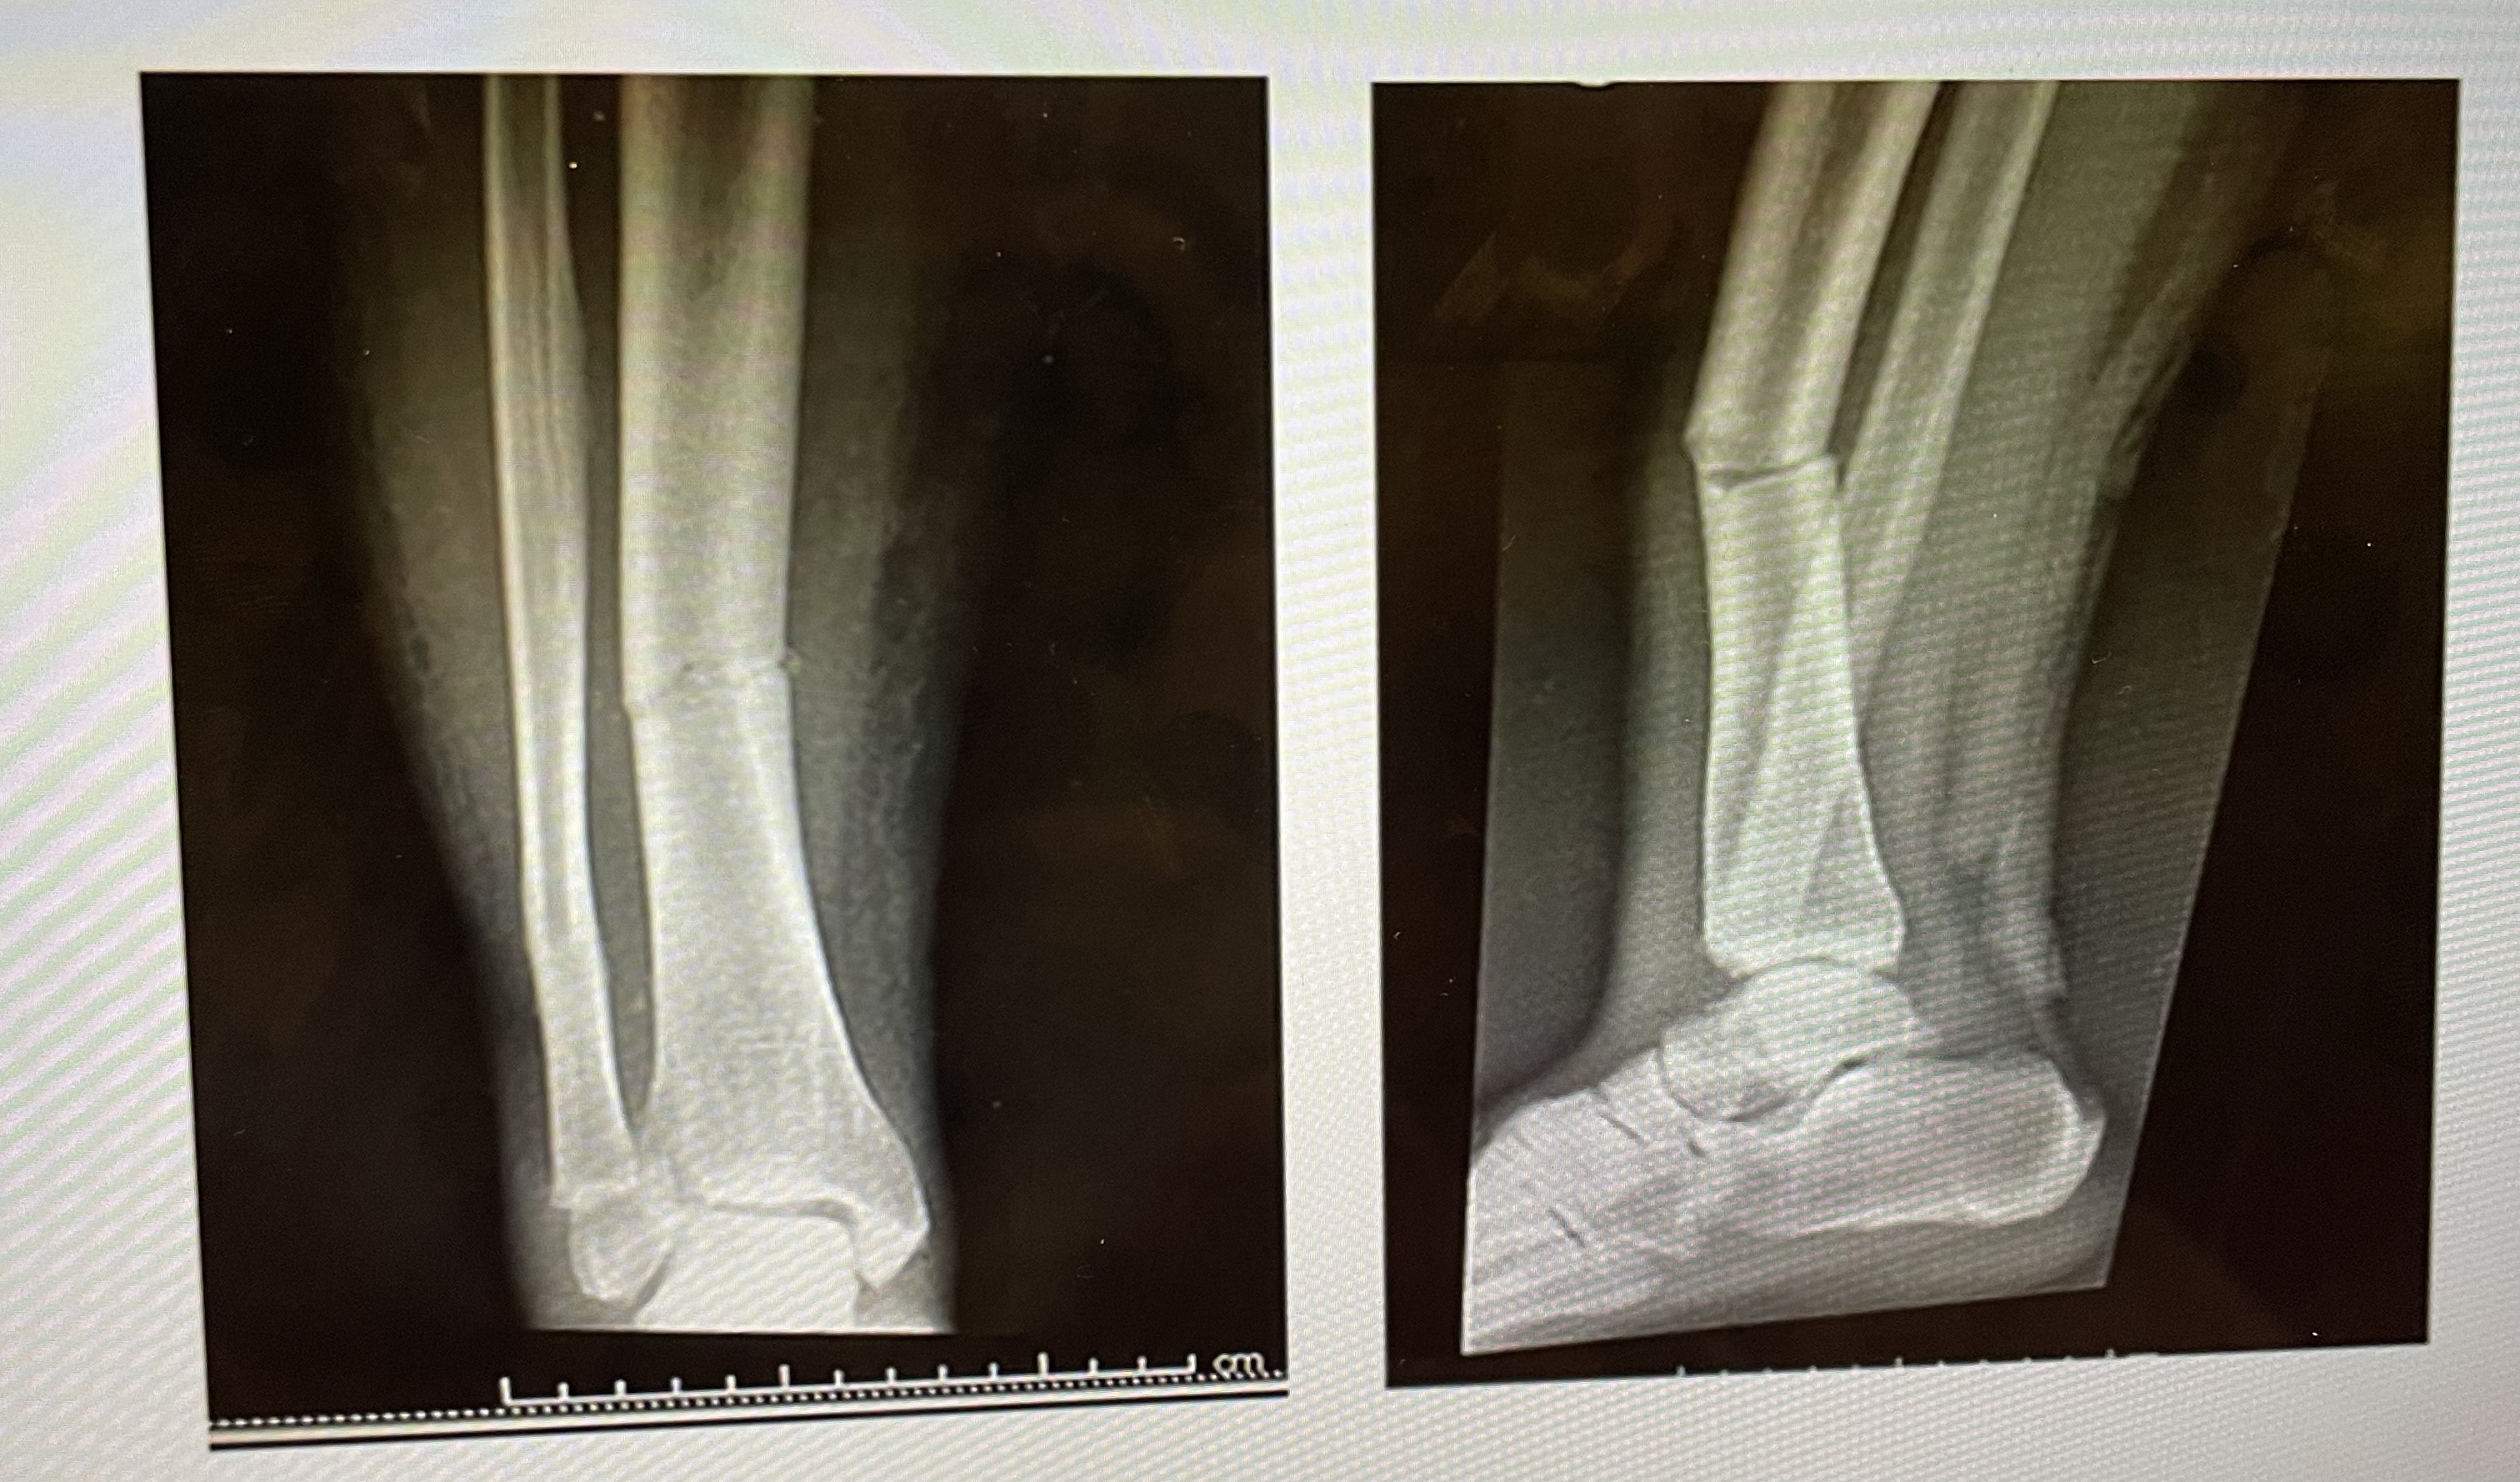

Based on your knowledge of bones, the fractured bone here is the

Right tibia